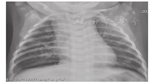

实验室检查:血常规示白细胞为(17.18~27.00)×109/L,血红蛋白、血小板正常,C反应蛋白最高135 mg/L;肝肾功能正常,降钙素原0.42 μg/L;血免疫球蛋白IgM 、IgG 、IgA、IgE正常;流式淋巴细胞亚群分类均正常;铁蛋白1 111 μg/L。血巨细胞病毒抗体阴性,1,3-β-D葡聚糖(G试验)阴性,血清半乳甘露聚糖(GM试验)2.13 μg/L(正常范围0~0.85 μg/L),γ-干扰素释放试验、血培养阴性。痰抗酸染色、真菌荧光染色、痰培养均阴性。胸片示双肺多发片状高密度影(图1)。胸CT平扫及强化示双肺多发软组织密度团块影及结节影伴边缘强化,纵隔内、右侧肺门及双侧腋窝多发淋巴结影并部分增大(图2)。胸部彩超示右侧胸腔实性包块,范围7 mm×26 mm×23 mm,考虑肺脓肿。

多数CGD患者起病于感染,常初诊于呼吸科或消化科。本例患儿新生儿期起病于侵袭性曲霉菌感染引起的发热,进展为肺脓肿,合并皮肤毛囊炎性丘疹,临床主要表现为发热,肺部影像学为特征性的多发团块影、结节影伴边缘强化。与文献报道的X-连锁隐性CGD临床表现相似[4],肺炎最常见,其他依次为淋巴结炎、腹泻、脓肿、骨髓炎、肺结核等,还有IBD、自身免疫性疾病等。极早发炎症性肠病(very early onset IBD,VEO-IBD)有一部分可归为原发性免疫缺陷病[5]。文献复习101例NCF2基因突变的CGD表现有IBD者5例[6,7,8],均在出生6个月内出现慢性腹泻或便血,在出现反复严重感染之前,易被误诊为牛奶蛋白过敏或因合并自身免疫性疾病而诊断延迟,对VEO-IBD尤其2岁以内起病的患者,应进行CGD和其他免疫缺陷病的评估。